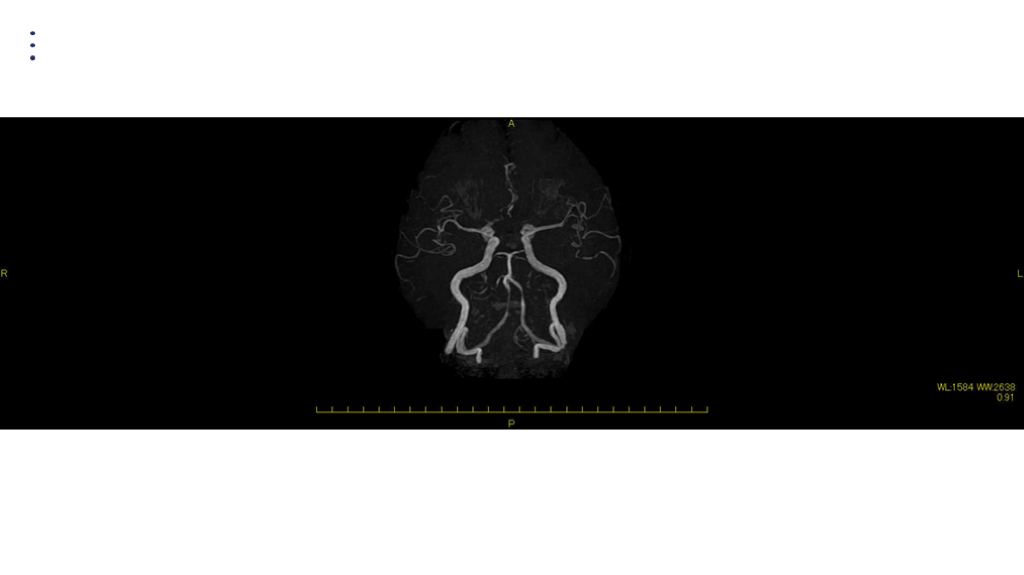

画像 所見 DAY 14 MRA 悪化